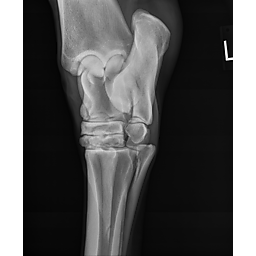

**Tex sells at the Colorado Horse Sale's Best of the West Select Sale on May 30th in Castle Rock, CO - He will complete the riding & handling Sift Exam, baseline veterinary exam, and will sell with 4 total radiographs (DLPMO & Front Foot Lateral)**